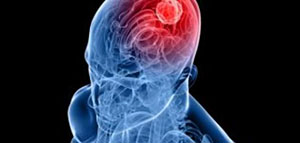

الأمراض العقلية و أنواع الأمراض العقلية